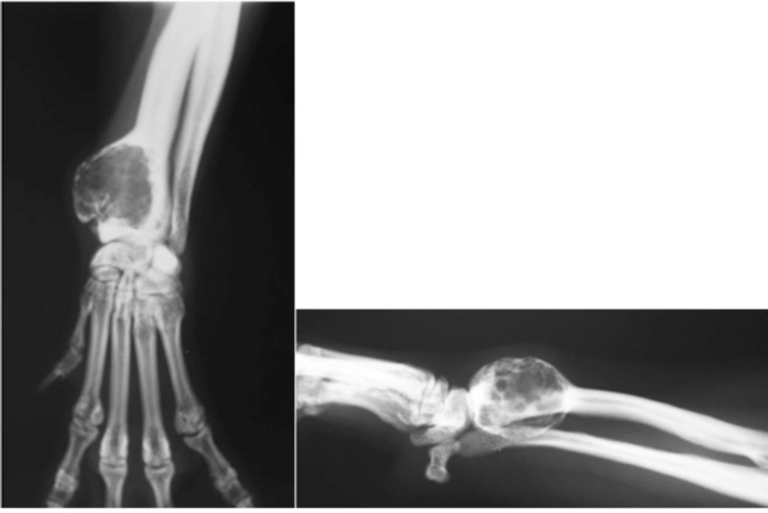

From www.semanticscholar.org

Figure 1 from Solitary Bone Cyst Traumatic Cyst , Hemorrhagic Cyst Do Bone Cysts Need To Be Removed The surgeon may suggest this if a cyst has caused major damage to the. If a pathologic fracture occurs, the cyst may need to be surgically cleaned and then packed with bone graft to fill in the bone and encourage bone healing. Although they can develop in any bone, ubcs usually affect the long bones — most often the upper. Do Bone Cysts Need To Be Removed.

From www.researchgate.net

A Radiograph demonstrated features of simple bone cyst at the initial Do Bone Cysts Need To Be Removed The surgeon may suggest this if a cyst has caused major damage to the. Unicameral bone cysts (ubc) are cavities within bone that are filled with fluid. If you find out you have a cyst after you break a bone, you may need to. Rarely, doctors will need to remove part of the bone, beyond the cyst. If a pathologic. Do Bone Cysts Need To Be Removed.